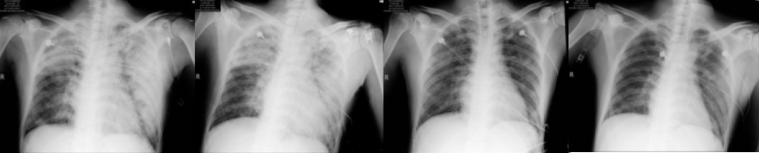

患者,男,47岁,因“咳嗽1月余,气促20余天,加重伴发热5天”,于2017年12月11日入我院。入院1月余前无明显诱因开始出现咳嗽、咳痰,为白色泡沫痰,无气促、咯血、呼吸困难,至当地医院经抗感染治疗后(具体不详)无好转,症状进行性加重。入院前20天出现活动后气促、呼吸困难,于2017年12月3日至广东某医院,查颈部+胸部+颅脑CT提示:左右肺纹理增多、增粗,见点索状、小片状、结节状增密阴影,边界模糊,考虑肺泡癌?转移瘤?炎症?纵隔多发肿大淋巴结,考虑转移瘤;心包积液;双侧胸腔积液;肝内多发病灶,考虑转移瘤(图1)。

2017年12月6日就诊于中山大学肿瘤防治中心,查WBC14.73×109/L,D-二聚体37.17 μg/ml。胸部CT提示:右下肺门区软组织影并右下肺阻塞性肺炎、肺不张,右下肺前外基底段胸膜下结节,考虑原发肺癌与转移瘤相鉴别;双肺叶弥漫粟粒、类结节,考虑转移瘤;双肺多发斑片影,部分呈磨玻璃密度,考虑炎症;双侧锁骨上窝、纵隔、双肺门多发淋巴结,考虑转移瘤;右侧颈静脉-右侧锁骨下静脉-右无名动脉内充盈缺损,考虑血栓可能性大,左肺动脉可见栓塞(血栓或癌栓)(图2)。